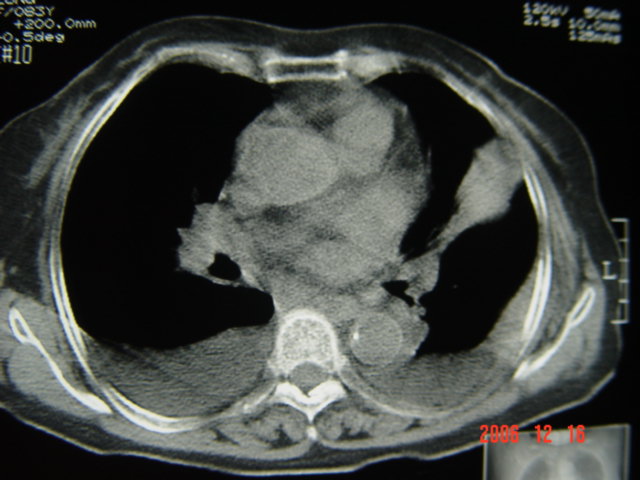

标题: CT5663:女、83岁,轻微咳嗽、左下胸痛。 [打印本页]

标题: CT5663:女、83岁,轻微咳嗽、左下胸痛。

左第八肋腋侧呈膨胀性骨质破坏,内侧见软组织密度肿块。左肺舌段呈楔形实变,基底近胸壁,尖端向肺门。双侧胸壁后缘见新月形水样密度区。

考虑:1、左第8肋骨转移瘤;

2、左肺舌叶肺栓塞可能性大;

3、双侧中量胸腔积液。